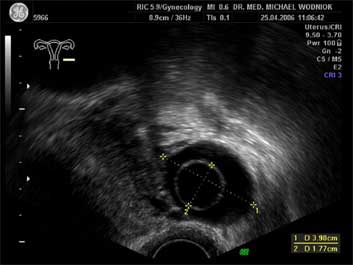

Ultraschall des kleinen Beckens mit der Vaginalsonde Die Ultraschalluntersuchung ist ein bildgebendes Verfahren, welches die Reflektion oder Echos von Ultraschallwellen in den unterschiedlichen Geweben und Organen ausnützt um computergestützt Schnittbilder aus dem Inneren des Körpers zu erstellen. Durch moderne hochleistungsfähige Mikroprozessoren ist es in den letzten Jahren möglich geworden, auch 3-dimensionale oder sogar bewegte 3-dimensionale (4-D) Bilder bzw. Bildsequenzen zu erzeugen. Beides können wir Ihnen in der Praxis anbieten. Eine Ultraschalluntersuchung ist ungefährlich und schmerzfrei. Durch die Anwendung von Dopplerverfahren, mit welchen wir den Blutfluss in den Organen feststellen und messen können, erweitern wir die Untersuchung um die funktionelle Dimension. Ein weiterer Bestandteil unseres Leistungsspektrums ist die farbkodierte Dopplersonographie. Farbkodiert sind entweder die Richtung des Blutflusses oder dessen Intensität. Über die computergestütze Berechnung des Blutflusswiderstandes ist im Einzelnen eine Aussage bzw. Vorhersage über die qualitative und quantitative Durchblutung möglich. (Plazentadurchblutung, kindliche Blutgefässe, Durchblutungsmuster bei verschiedenen Tumoren des Unterleibes und der Brustdrüsen) Ultraschalluntersuchungen haben in unserem Fachgebiet vielfältige Anwendungsmöglichkeiten gefunden. Besonders faszinierend ist der Einsatz im Bereich der vorgeburtlichen Diagnostik. Bereits in der 10. Schwangerschaftswoche ist es möglich, die Extremitäten des Embryos darzustellen und Aussagen zum Körperumrissbild zu machen (Ausschluss von Spaltbildungen, Nackentransparenzmessung). Auch im Bereich der Gynäkologie ist die Bedeutung des Ultraschalls stetig gewachsen und hat sich als erweiterte Vorsorge etabliert. Durch die vaginale Ultraschalluntersuchung können bereits kleine Veränderungen entdeckt werden, die sich der manuellen Tastuntersuchung noch entziehen. Auffällige Tastbefunde an den Eierstöcken sind durch den Einsatz von 3D / 4D in Kombination mit der Farbdoppleruntersuchung besser interpretierbar und können dadurch Frauen unnötige abklärende Operation ersparen. Die Anwendung des 3D Ultraschall, insbesondere im Coronarschnitt, lässt eine effektive Beurteilung für Veränderungen (Polypen, Karzinome) der Gebärmutterschleimhaut zu. ![]() ![]() ![]() ![]() ![]() |